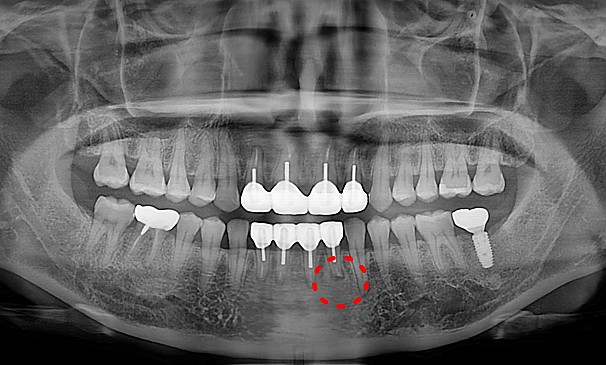

강OO님 전후사진 | 치료 기간 : 1주

치료 전

치료 후

뿌리염증제거술